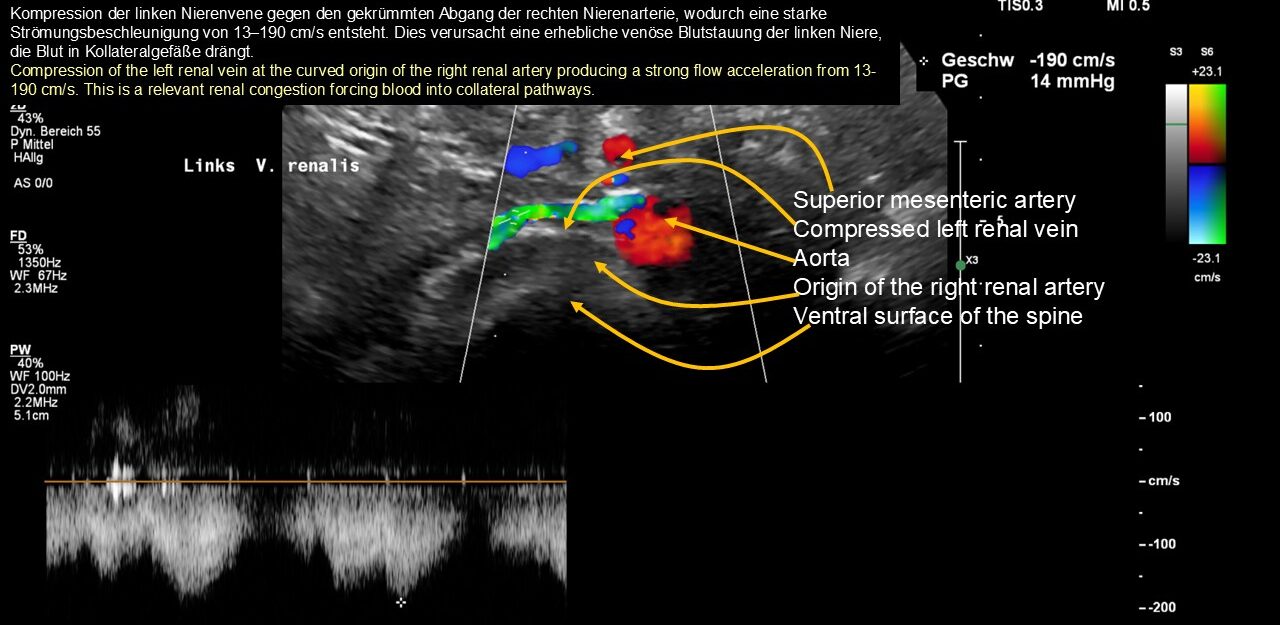

- eine hochgradige Kompression der linken Nierenvene

Der klinisch vermutete und intraoperativ bestätigte Tronc réno-rachidièn konnte zunächst sonographisch nicht visualisiert werden, da aufgrund des hohen Staudrucks im Spinalkanal kein effektiver Blutfluss vorhanden war, der ein Doppler-Signal erzeugt hätte. Dies war Ausdruck des enormen intraspinalen Drucks, der dem Druck in der komprimierten linken Nierenvene entsprach.

Darüber hinaus wurde der Stauungsdruck im Spinalkanal durch große Blutmengen über die aufsteigende Lendenvene links erhöht, was zu neurologischen Ausfällen in Form einer extrem schmerzhaften Spastik im linken Bein führte.

Die spastische Innenrotation des linken Beins wird durch eine venöse Stauung des Rückenmarks im Wirbelkanal verursacht, während die entlang des Ischiasnervs ausstrahlenden Schmerzen durch eine schwere Obstruktion des Abflusses in der linken inneren Beckenvene verursacht werden, die den venösen Rückfluss aus dem Ischiasnerv über die linke untere Gesäßvene fast vollständig stoppt.

Die Schmerzen bei der Nahrungsaufnahme ließen sich leicht durch den erhöhten Druck erklären, den der sich füllende und vergrößerte Magen auf die massiv gestaute linke Nierenvene hinter dem Magen während der oralen Nahrungsaufnahme ausübte. Aus klinischer Sicht bestand auch eine Kompression des Zwölffingerdarms (Wilkie-Syndrom), die zu sofortigem Erbrechen nach der Nahrungsaufnahme in Kombination mit starken Schmerzen im Oberbauch führte.